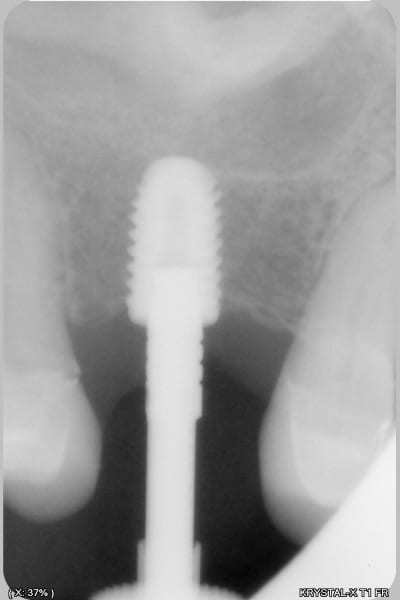

donc tu avais raison Enlaye... le bridge à cassé (sur un carambar quand même:-))

dépose, nettoyage sablage des couronnes récupérable et pose d' implant, uniquement en manuel (os tendre)